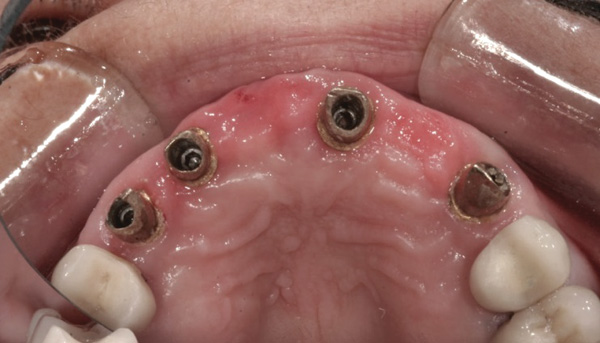

Background: In this case, the patient had a failing mandibular and maxillary dentition due to caries secondary to radiation-induced xerostomia. The patient had had a radical neck dissection to remove a squamous cell carcinoma of the throat 9 years prior to his prosthodontic consultation with the authors. The patient reported a history of radiation therapy following surgery, but did not have a shielding stent. A staged approach was used so as to avoid removable prosthetics on his severely dry soft tissues. He chose to treat his mandibular issues first. Figure 9 shows healing abutments next to the temporarily retained natural teeth, and Figure 10 shows the first-stage custom abutments inserted with relatively good gingival contour and no recession. Recession was clearly seen around all first-stage abutments following adjacent extractions and second-stage implant placement (Figure 11).

Figure 9 Healing abutments.

Figure 9

Figure 10 First-stage custom abutments.

Figure 10

Figure 11 Recession evident around first-stage abutments following adjacent extractions and second-stage implant placement.

Figure 11